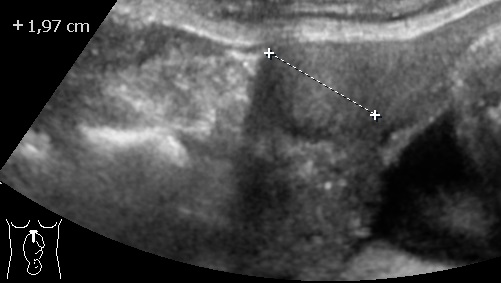

Multiple Myomas in pregnancy 3